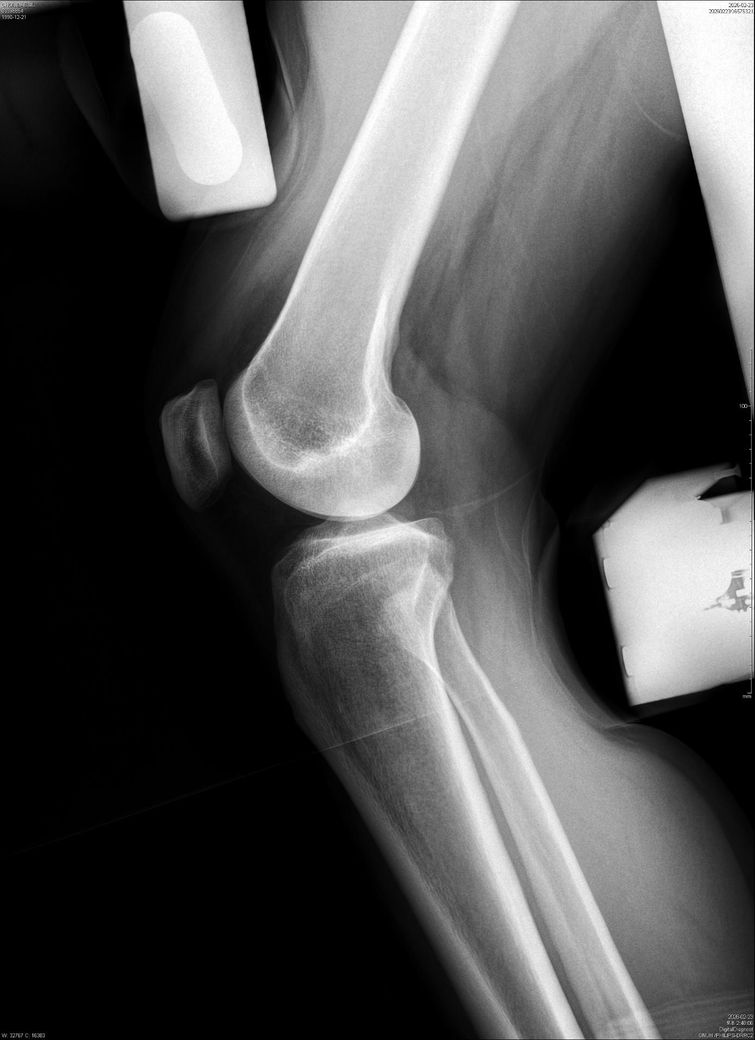

• 4번 째 사진

이 X-ray는 뼈 정렬·고정물 위치만 볼 수 있어, “무릎 동요도(십자인대 안정성)”는 판단할 수 없습니다.

동요도는 Lachman, Pivot shift 같은 이학적 검사나 MRI로 확인해야 합니다.

수술 6개월 후에도 통증이 지속되면 인대 이완, 반월상연골 재손상, 연골 손상 가능성도 있습니다.

정형외과에서 직접 진찰 + 필요 시 MRI를 꼭 권유드립니다.

단순 엑스레이 사진만으로는 무릎 동요도를 측정하기 어렵습니다.

전문 장비를 이용한 검사나 스트레스 엑스레이등을 이용한 평가를 통해 확인하시는 것을 추천드립니다.